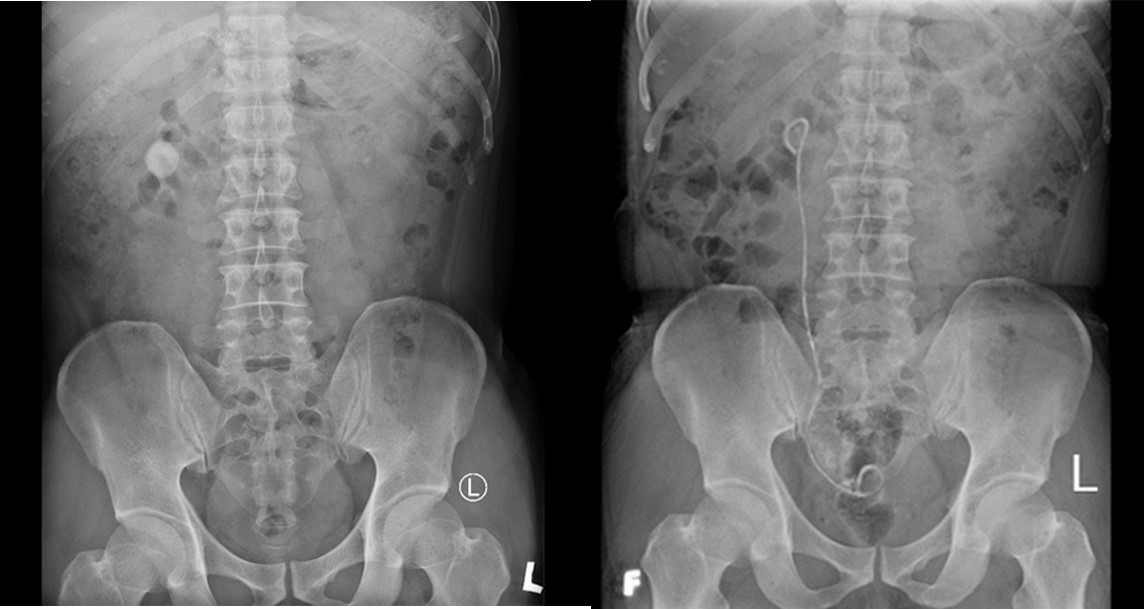

Hình 2: X- Quang hệ tiết niệu của bệnh nhân trước và sau mổ

Bệnh nhân được tiến hành phẫu thuật tán sỏi thận P qua da ngày 16/5.

BN rút sonde dẫn lưu và xuất viện sau 3 ngày.